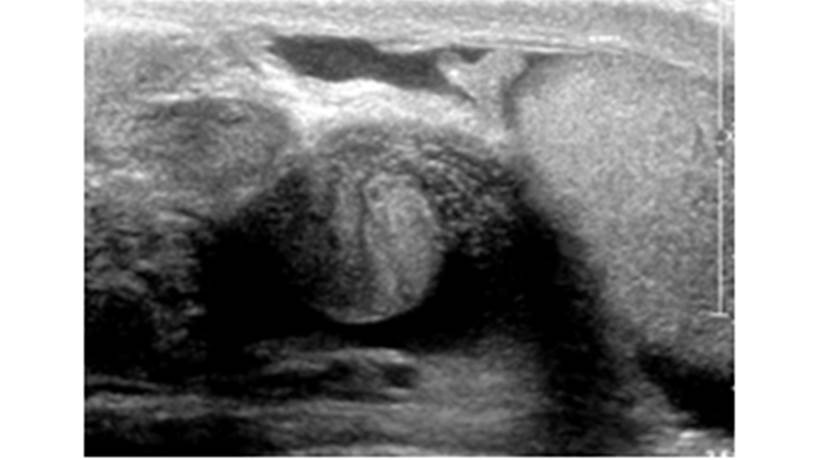

A la exploración física se encuentra al testículo izquierdo fuera de la posición habitual, ascendido, transversal y muy doloroso. Se le realizó ultrasonido Doppler en el que se observó el testículo izquierdo de dimensiones 42 x 25 x 39 mm con cambios de la situación anatómica habitual, el eje mayor desviado hacia la línea media, con bordes regulares y bien definidos, con un parénquima heterogéneo con áreas hiperecoicas puntiformes dispersos y aislados compatibles con microcalcificaciones, con abundante líquido anecoico peritesticular compatible con hidrocele reactivo y el cordón espermático con trayecto serpiginoso, con signo del remolino en los cortes transversales (Fig. 1).

Figura 1. Ultrasonido de testículo que muestra testículo izquierdo de dimensiones 42 x 25 x 39 mm con cambios de la situación anatómica habitual, con su eje mayor desviado hacia la línea media, con bordes regulares y bien definidos, con un parénquima heterogéneo con áreas hiperecoicas puntiformes dispersos y aislados compatibles con microcalcificaciones, con abundante líquido anecoico peritesticular y el cordón espermático con trayecto serpiginoso, con signo del remolino en los cortes transversales.

Figura 1 Ultrasonido de testículo